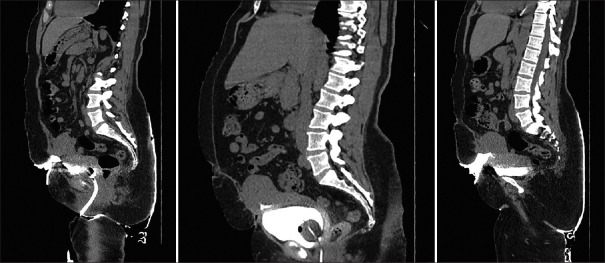

This case report presents the diagnosis and management of a 41-year-old woman who developed a vesicouterine cutaneous fistula after a cesarean section. She initially presented with pus discharge from the cesarean wound site, and later exhibited cyclical hematuria and fluid leakage from the skin incision, prompting further investigation. Diagnostic modalities, including computed tomography with contrast, confirmed the presence of a complex fistula involving the bladder, uterus, and skin. Conservative management with gonadotropin-releasing hormone therapy was attempted but discontinued due to worsening symptoms. Surgical intervention was performed successfully, leading to the resolution of symptoms. This case underscores the importance of prompt recognition and appropriate management of rare postcesarean complications, emphasizing adherence to anatomical principles.